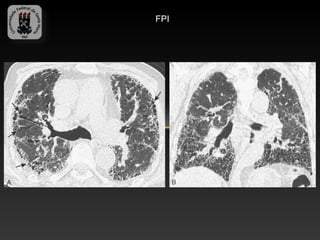

-FIBROSE PULMONAR IDIOPÁTICA

-É a PII mais comum, com sobrevida desde o início da dispnéia de 3 a 6

anos.

-Mais frequente em pacientes com mais de 50 anos

-Achados TC:

-   Atenuação reticular fina simétrica, com opacidades intralobulares

-   Espessamento septal interlobular

-   Bronquiectasia de tração

-   Vidro fosco e faveolamento

-Diag. diferencial: asbestose, d. colagenovasculares, PH crônica e

sarcoidose.

FPI